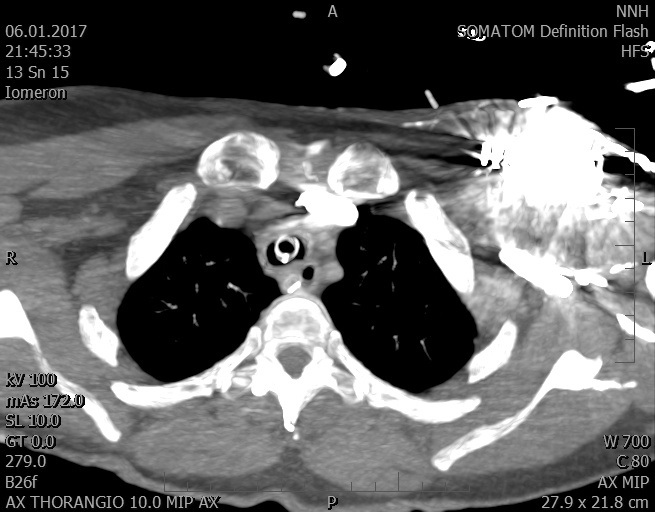

Video 2 - Echokardiograficky byla zjištěna těžká dysfunkce dilatační levé komory s nezvětšenou pravou komorou.Pro nejasnou příčinu zástavy jsme provedli i vyšetření výpočetní tomografií (CT), které vyloučilo plicní embolizaci (série 1 - soubory na konci článku). V den přijetí při přetrvávající oběhové nestabilitě byla nemocná opakovaně defibrilována pro fibrilaci komor se stabilizací rytmu po podání amiodaronu a mesocainu. Dle hemodynamických měření se jednalo o těžký kombinovaný šok. Vstupní laboratorní vyšetření bylo bez větších pozoruhodností. Posléze jsme doplnili anamnézu od příbuzných a zjistili, že pacientka užila do dvou hodin před srdeční zástavou první tabletu amoxicilinu na lehký respirační infekt. Při nevýtěžnosti vstupních vyšetření a nových anamnestických informacích jsme doplnili 14 hodin po kolapsu vyšetření koncentrace tryptázy v séru, která byla extrémně zvýšena (tabulka 2), což nás vedlo k podezření na anafylaxi.